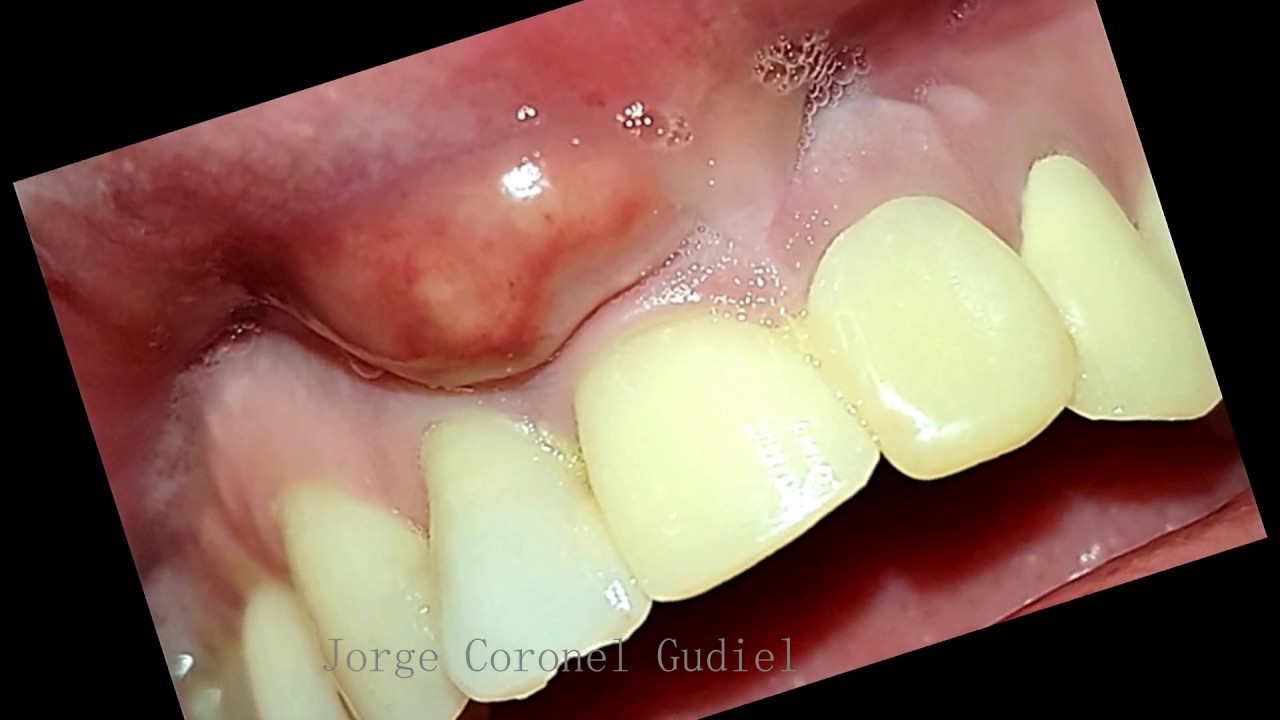

Absceso dental. Closeup de un absceso en la boca de un paciente dental Absceso Dental Que Tomar En el consultorio del dentista, el tratamiento para un absceso gingival. Además de examinar el diente y el área alrededor de este, el dentista puede hacer lo siguiente:. también conocido como flemón dental, el absceso debe tratarse cuanto antes y no solo por la aflicción que supone, sino por el daño que causa en las estructuras internas del diente.. Absceso Dental Que Tomar.